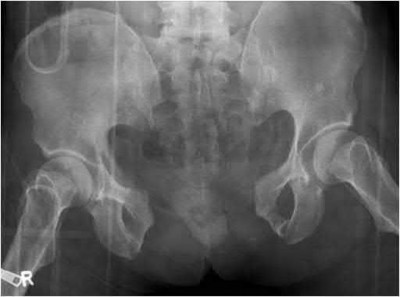

A 75-year-old man underwent total hip arthroplasty 10 years ago. He now reports mild groin pain which has been increasing lately. What is the most likely explanation for the finding in Figure A indicated with the arrows?

Osteolysis of the pelvis is a common complication associated with total hip arthroplasty. Osteolysis affects sockets with and without cement, and has been attributed to the biologic reaction to wear debris. With well-fixed cementless sockets, an expansile pattern of osteolysis is usually seen.

The radiographic appearance has a radiolucent area that starts at the implant-bone interface and expands into the cancellous bone away from the implant.

This pattern of osteolysis can be explained with the concept of effective joint space. This concept states that joint fluid and wear particles will flow according to pressure gradients and follow the path of least resistance.

The Level 5 review article by Chiang discusses osteolysis in further depth.